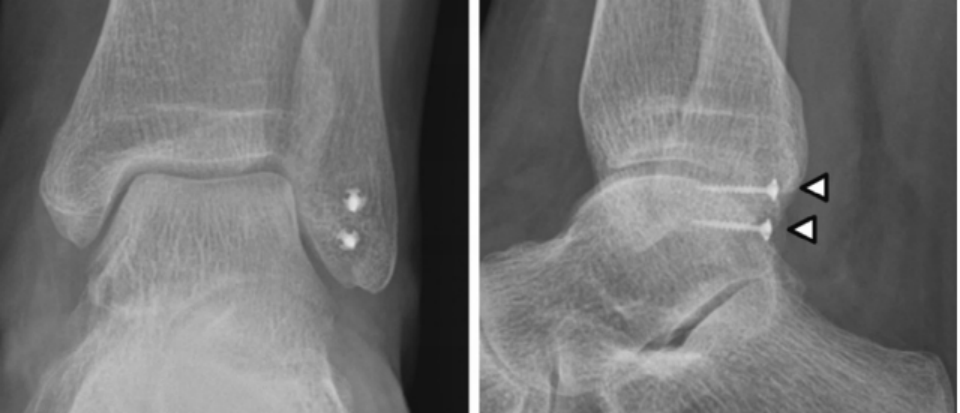

X线检查:腓骨肌腱脱位伴腓骨撕脱骨折(斑点征)有一定的诊断意义。

CT∶可显示腓骨外侧窝的解剖形态、腓骨撕脱骨折及腓骨肌腱的位置。

SPR撕脱开放手术锚钉修复

通过切除腓骨后方部分骨质,可以加深腓骨沟,改变、并增加了腓骨肌腱的稳定。